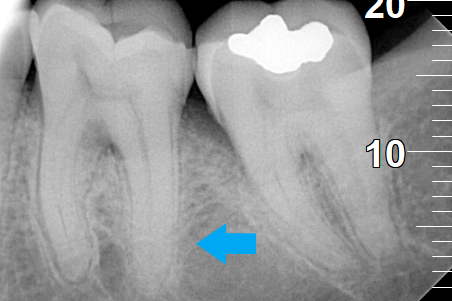

BEFORE

AFTER